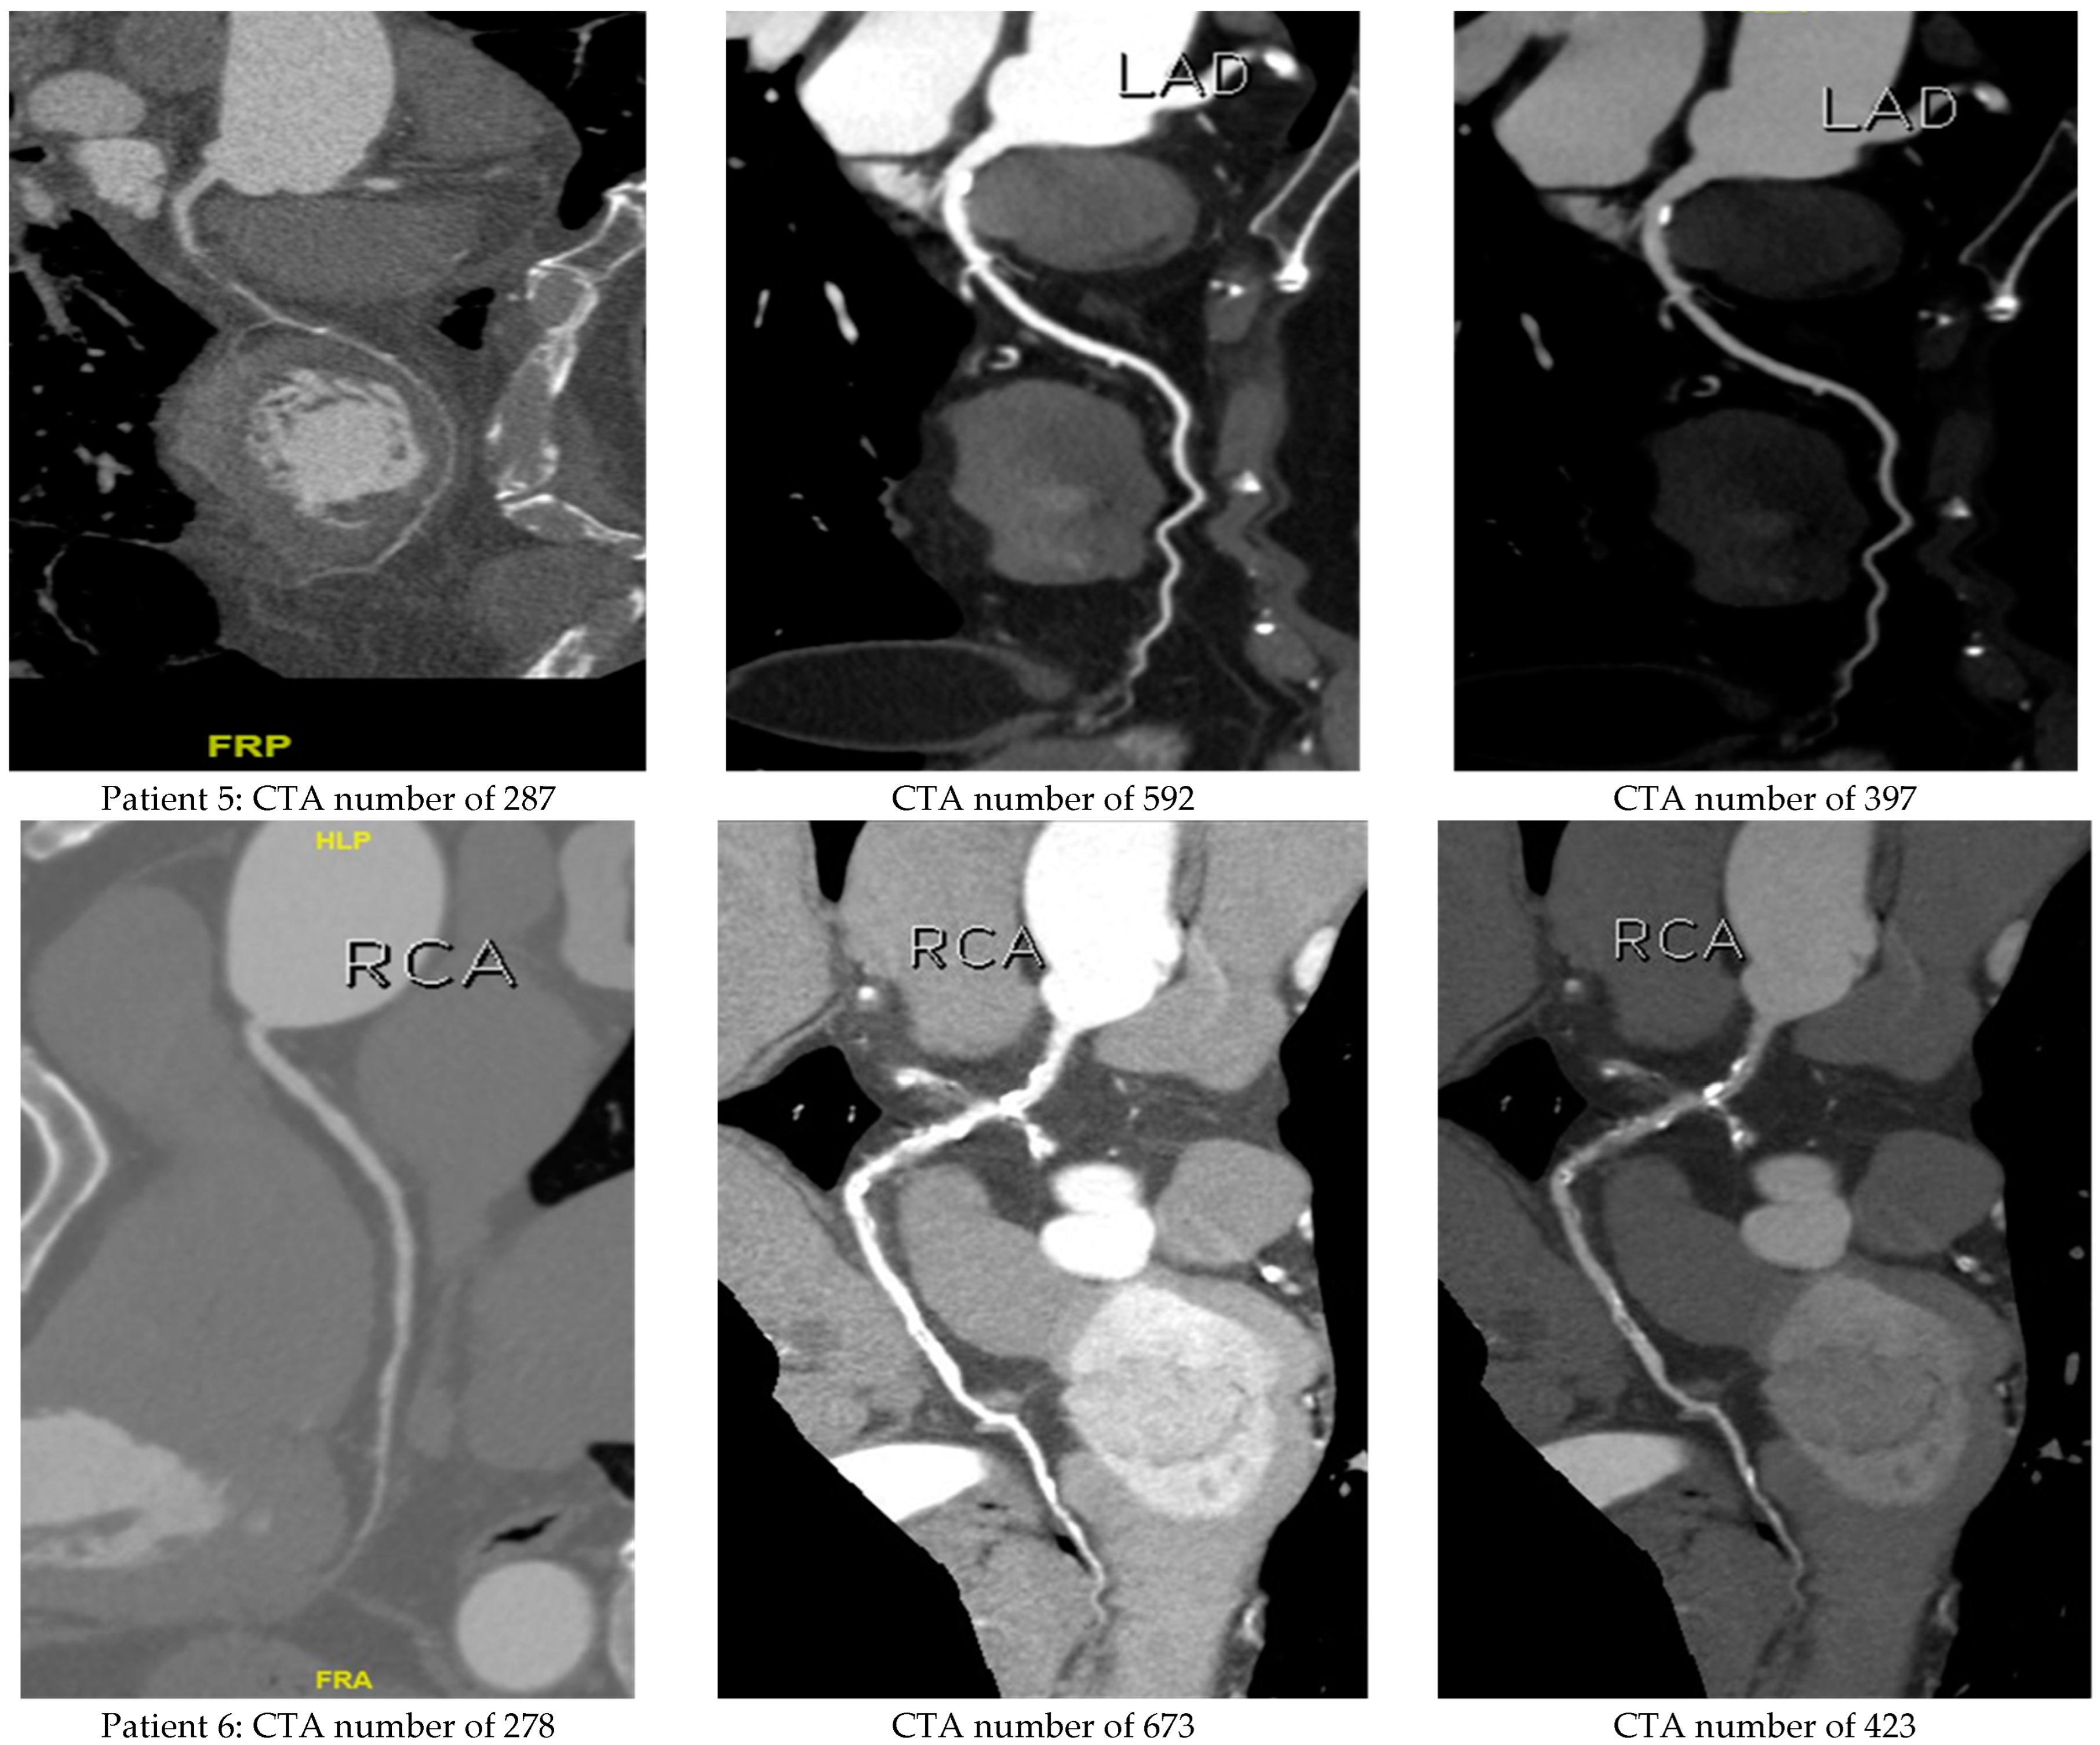

4.1. Verifying the Predicted CTA Number of LA by the Derived Semi-Empirical Formula

4.3. In Vivo Testification of 65 Patients